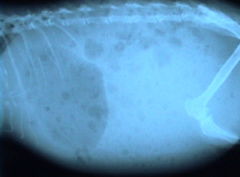

食欲不振で物を食べていないのに、レントゲンで胃内に異物があれば異常です。これは胃内に300ml位の胃液がたまって胃の出口で毛球が詰まってました。 |

診断には触診で胃内に毛球が確認できる場合もありますが、たいていはX線写真にて確認できます。食事をしていないのに胃内に内容物があれば異常です。それでも診断が付かない場合はバリュウム検査を行います。胃の通過時間や、バリュウムが付いた毛玉が胃内に長時間停滞しているのが観察できるはずです。

| 毛自体は細くて柔らかいですが、胃酸では消化出来ないために、一度に大量に飲み込むと絡まってしまいます。写真のような直径2〜3cmほどの毛玉でも腸では詰まってしまいますので、致命的になります。 |